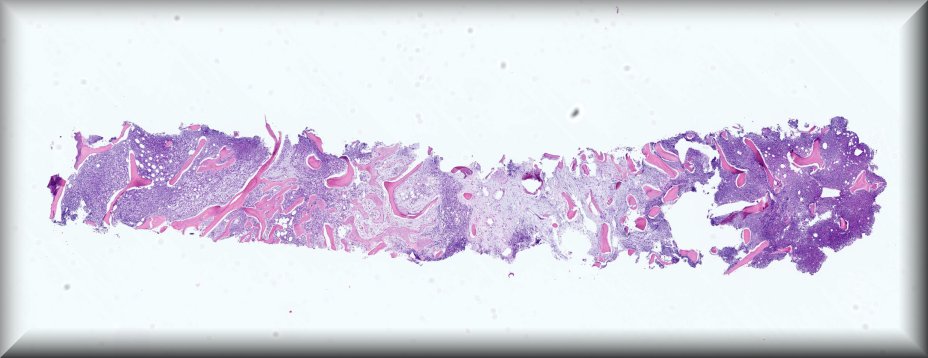

Caso 1.- María José Naharro Gascón, Julieta Romina Arbat, Elizabeth Burch Nchama, Amparo Taverner Lino, Encarna Marti Ibor, Maria Luisa Pérez Ebri.

Hospital Doctor Peset de Valencia.

Varón de 44 años que consulta por múltiples adenopatías en regiones inguinal y pélvica, que en el estudio PET-TC muestra captación e hipermetabolismo en esternón y escápula en relación a posible infiltración de médula ósea. Además, presenta en rodilla derecha a nivel cutáneo una lesión nodular indurada y violácea, de 1 cm de tamaño. No presenta afectación del estado general ni síntomas B. En el estudio por sospecha de neoplasia hematológica se realiza biopsia de médula ósea.